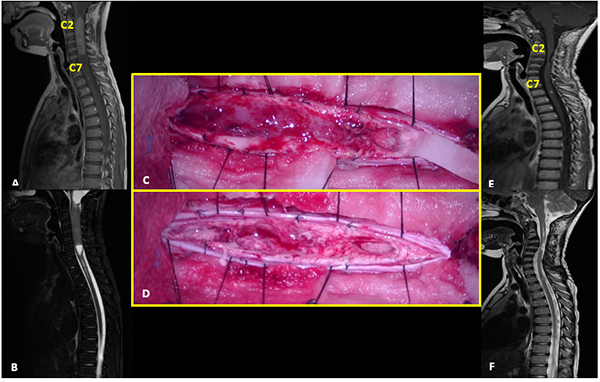

III: Astrocitoma Pilocítico

Paciente sexo femenino de 17 años con antecedente de trastornos de la conducta alimentaria que consulta por disestesias en palmas y plantas de un año de evolución, que progresa con debilidad en miembro superior izquierdo. Al examen físico se evidencia paresia leve braquial izquierda. La RM mostró dos lesiones focales hiperintensas en T2, localizadas en el cordón posterior derecho, que comprometen los niveles C2 y C3-C4 que no presentan realce tras la administración de contraste. Se realizó exéresis completa de lesión inferior y subtotal de la superior. El monitoreo neurofisiológico intraoperatorio no evidenció alteraciones significativas en los potenciales motores. En el postoperatorio inmediato la paciente recuperó la paresia del MSI. La RM control confirma remanente tumoral a nivel de C2 y resección total de la lesión C3-C4. La anatomía patológica informó astrocitoma pilocítico (Grado I de la OMS). La paciente evolucionó con inestabilidad cervical y cifosis progresiva requiriendo artrodesis cervical anterior (C3-C5) a los 7 meses de la cirugía (Figura 3).

Figura 3: Astrocitoma Pilocítico. A-C: RM prequirúrgica T2 cortes axiales y sagitales. D-F: Imágenes intraoperatoria pre y postresección. G-I: RM postquirúrgica T2 cortes axiales y sagitales. J-K: Radiografía cervical frente y perfil post-instrumentación.